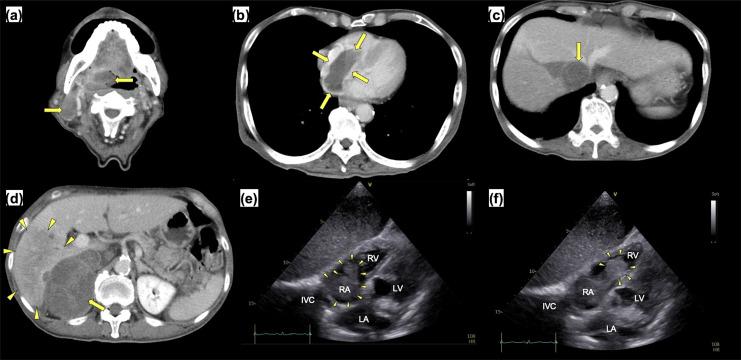

一名 78 岁的日本老人因咽喉痛和发烧到急诊科就诊,3 周后病情加重。扁桃体活检后确诊为多形性套细胞淋巴瘤(MCL),已浸润右肾上腺、下腔静脉和右心房(RA)。虽然患者的心脏肿瘤具有很高的移动性,但他的血流动力学状态稳定,没有出现致命性心律失常。因此,我们首先进行了化疗。然而,患者出现了复发性肺栓塞(PE),并在开始化疗后死亡。尸检显示,MCL 侵犯了大血管,导致了肺栓塞。尽管众所周知心脏肿瘤的高流动性会增加弥漫大B细胞淋巴瘤(DLBCL)发生肺栓塞的风险,但由于其罕见性,心脏MCL的最佳治疗方法仍有待阐明。据我们所知,这是日本患者首次报告治疗后出现 PE 的心脏 MCL。不仅是 DLBCL,基于心脏肿瘤的流动性,MCL 也值得考虑在治疗前进行预防性手术。我们的病例强调了血液科医生和心脏科医生在治疗心脏型 MCL 时密切沟通的必要性。

A 78-year-old Japanese man presented to the emergency department with a sore throat and fever that worsened over 3 weeks. A tonsil biopsy led to the diagnosis of pleomorphic mantle cell lymphoma (MCL) that had infiltrated the right adrenal gland, inferior vena cava, and right atrium (RA). Although the patient's cardiac tumor had high mobility, his hemodynamic state was stable, and he did not present with fatal arrhythmia. Therefore, we first introduced chemotherapy. However, the patient developed recurrent pulmonary embolisms (PEs) and died after starting chemotherapy. An autopsy revealed that the MCL had invaded the large vessels, causing the PEs. Although the high mobility of cardiac tumors is known to increase the risk of PE in diffuse large B-cell lymphoma (DLBCL), optimal management of cardiac MCL remains to be elucidated owing to its rarity. To the best of our knowledge, this is the first report of cardiac MCL with posttreatment PE development in a Japanese patient. It is worth considering preventive surgery before treatment not only in DLBCL, but also in MCL based on the mobility of the cardiac tumors. Our case highlights the need for close communication between hematologists and cardiologists to treat cardiac MCL.